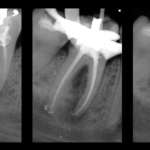

Lesione endo-parodontale complicata da una perforazione da stripping. Case report

In questo case report, relativo al trattamento di una lesione endo-parodontale di un molare, la scelta del file errato ha causato la perforazione e...